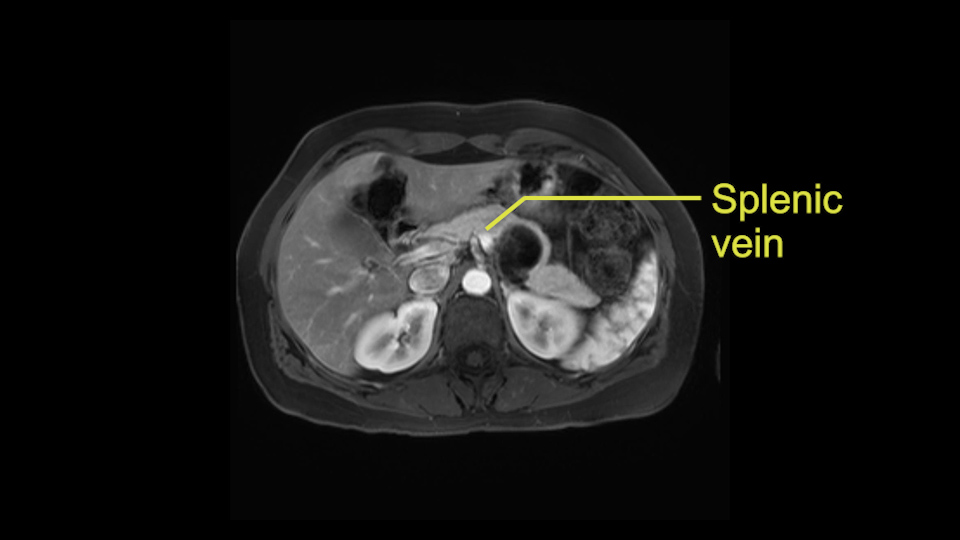

Tumor proximity to splenic vein

The lesion itself is quite adjacent to and abuts the splenic vein and therefore we need to anticipate that these two structures will be intimately related and possibly impossible to separate between the two.

The second slowing down moment or consideration I give to a distal pancreatectomy is the anatomy of the portal vein and the splenic artery. And so I look here and the anatomy is pretty straightforward. The splenic vein comes off normally and runs behind the pancreas and I can see the artery superior to that, again coming off in a normal manner from the celiac axis. So those two things, the portal vein and the splenic artery will be taken normally in this procedure.

So first step that we do: mobilize the splenic flexure first to visualize Gerota’s fascia and that would help bring down the colon and expose the pancreatic tail. So now that the pancreas is visible, division of the gastrocolic ligament will come into view. And a window can be created at the inferior edge of the pancreas to slowly lift the inferior edge to expose the splenic vein behind. This is the slow-down moment that I am talking about because the MR shows that there could be contact with the cyst. It’s important to know that to avoid perforation, to avoid rupture of the cyst, because we need to avoid touching the cyst, it is quite a size of 4.3 about 4cm.

I think the splenic vein, once I have slowly teased it off from the cyst and from the retropancreatic parenchyma, I would put a vessel loop around it to serve as a traction. So once you have the vessel loop or probably umbilical tape, to retract or pull the pancreatic parenchyma while we slowly tease it off and try to move superiorly to be able to expose the splenic artery. That is again another slow-down moment because sometimes we think that it is the splenic artery at the superior edge of the pancreas, but it could also be the hepatic artery as it branches from the celiac artery.